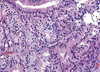

serous epithelileal tumor

39

serous epithelileal tumor, cystis linned epithelium,

40

mucinous epidermoid

41

brenner tumor

42

teratoma

43

dysgerminoma

44

granulosa cell tumors (call-exner bodies)

45

metastic tumor